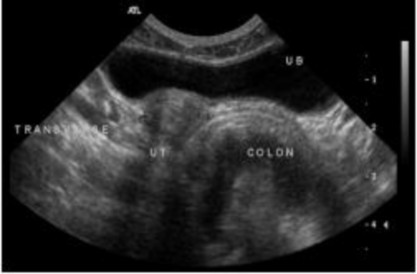

Nếu coi bàng quang như mặt đồng hồ, thân tử cung sẽ được đặt ở vị trí 5 giờ hoặc 7 giờ, ở một bên hoặc bên còn lại của đại tràng (Hình 2.8). Đặt đầu dò theo chiều ngang, bắt đầu ở giữa bụng và trượt theo chiều dọc cho đến khi hình ảnh ngang của bàng quang tiết niệu xuất hiện.

Hình 2.8. Hình ảnh cắt ngang của thân tử cung vị trí nhìn thấy ở giữa bàng quang tiết niệu (UB) và đại tràng

Nguồn: Rachel Pollard & Silke Hecht (2015)